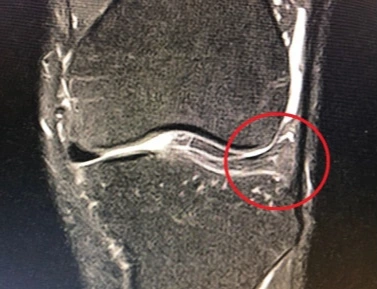

장기간 지속되는 찜찜함에 세심하게 대처했어야 했는데, 왼쪽 다리 길이가 오른쪽보다 짧아서 생긴 통증이라고만 생각했어. '꾸준히 하다 보면 익숙해져서 언젠가는 괜찮아지겠지.' 그렇게 안일한 태도로 계속했지. 한번은 결가부좌를 하는데 무릎에서 두두둑 소리가 났어. 통증이 없어서 대수롭지 않게 넘어갔지. 근데 다른 운동을 하면서 통증이 생기더니 점점 심해지더라구. 걸을 때도 지속되는 통증이 심상치 않아서 병원을 찾았어. 2020년 8월, MRI 검사로 왼쪽 무릎의 연골이 찢어졌다는 걸 알게 되었어.

정식 병명은 '반월상 연골의 파열'이야. 병원에서 MRI 사진 보고 설명 들을 때까지 사람 몸에 그런 연골이 있는 줄도 몰랐어. 반월상 연골은 허벅지뼈에 해당하는 대퇴골과 정강이뼈인 경골 사이에 있어. 무릎 안쪽에서 커다란 다리의 두 뼈 사이에 위치하면서 몸의 충격을 완충시켜 주는 연골이야. 이 연골 파열의 최대 단점은 완전한 치료가 어렵다는 거야.

반월상 연골의 파열은 찢어진 곳이 피가 통하는 부위면 봉합이 되지만, 그렇지 않으면 치료가 안돼. 그저 찢어진 부위를 깔끔하게 잘라내는 수준의 시술이 전부야. 의사들은 내 부위가 중증 이상으로 보이는데, 확실한 것은 속을 봐야 알고, 만약 봉합을 하더라도 가능성이 희박하다고 했어.